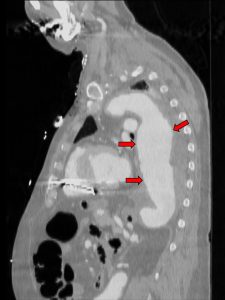

Aortenaneurysma: Neue Gefäßprothese soll Herzpatienten besser schützen18. Mai 2018 3-D-Druck-Modell eines Gefäßaneurysmas (weiß) und der Form der späteren Gefäßprothese (rot) in den Händen von Dr. Nikolaus Thierfelder, Herzchirurg. Klinik u. Poliklinik, Klinikum der LMU München. Foto: Andreas Steeger/Klinikum der LMU München Mediziner der Universitätsklinik München nutzen 3D-Druck-Technik für passgenauere Prothese bei Aortenaneurysma / Dr. Rusche-Projektförderung (60.000 Euro)Unbehandelt können sich aus Aneurysmen an der Aorta die höchst gefürchteten Dissektionen entwickeln – auch heute ein Notfall, der häufig tödlich endet. „Weil das erkrankte Gefäß ab einem bestimmten Durchmesser oder beim Auftreten von Beschwerden mit einer Prothese versorgt werden muss, sind auf diesem Gebiet Neuentwicklungen, die der Sicherheit und der Verbesserung der Lebensqualität der Betroffenen dienen, besonders wichtig“, betont Prof. Hellmut Oelert, Vorsitzender des Wissenschaftlichen Beirats der Deutschen Stiftung für Herzforschung (DSHF). Während der Eingriff früher nur mit Hilfe einer offenen Operation möglich war, lässt sich heute die Prothese in immer mehr Fällen katheterbasiert (minimalinvasiv) einsetzen. Es treten etwa 15 Fälle eines Aortenaneurysmas pro 100.000 Einwohner auf (Häufigkeitsgipfel im 6. und 7. Lebensjahrzehnt). Männer sind etwa 2- bis 4-mal häufiger als Frauen betroffen. Neue Prothese passt sich noch besser an die Gefäßanatomie des Patienten an Ein Forscherteam um den Herzchirurgen Dr. Nikolaus Thierfelder vom Klinikum der Ludwig-Maximilians-Universität München, Campus Großhadern, wird im Rahmen des mit rund 60.000 Euro geförderten Dr. Rusche-Forschungsprojektes* ein Verfahren entwickeln und testen, um künstliche Gefäßprothesen patientenindividuell herzustellen. „Unser Ziel ist es, durch die verbesserte Passgenauigkeit der Prothese die Komplikationsrate signifikant zu senken und gleichzeitig die Sicherheit für die Patienten zu erhöhen“, betont Thierfelder. Denn üblicherweise werden die Prothesen in bestimmten vorgefertigten Größen zur Verfügung gestellt, die der behandelnde Arzt nach Auswertung von Aufnahmen des erkrankten Gefäßes (z. B. Computertomographie) auswählt. „Dabei kann es vorkommen, dass die gewählte Prothese oft nicht ideal zur Anatomie des Patienten passt. Studien konnten zeigen, dass viele Komplikationen nach der Prothesenimplantation aus diesem Grund entstehen“, so Thierfelder. CT-Aufnahme eines Aortenaneurysmas. Quelle: Dr. Nikolaus Thierfelder/Klinikum der LMU München Komplikationen seien z. B. das Verrutschen der Prothese oder eine mangelnde Abdichtung an den Prothesenenden, die oft einen zusätzlichen medizinischen Eingriff erforderten. Als Grundlage zur patientenindividuellen Prothesenproduktion dienen CT- oder MRT-Aufnahmen, die im Zuge der Diagnostik vor dem Eingriff ohnehin gewonnen werden müssen. Plastisches 3D-Druck-Modell des erkrankten Gefäßes In einem mehrstufigen Prozess, können aus den Aufnahmen mit Hilfe einer spezialisierten Software anatomische Strukturen (z.B. das erkrankte Gefäß) definiert und freigestellt werden. Die erkrankten Stellen des Gefäßes werden ausgewählt, modifiziert und anschließend mit Hilfe eines 3D-Druckers als plastisches Modell hergestellt. Auf dieses Modell wird dann mit einem elektronischen Spinnverfahren („Elektrospinning“) eine dünne, faserige Polymerschicht aufgetragen. Die neu entwickelte patientenspezifische Prothese wird nicht nur aus einem Kunststoffschlauch wie bisherige Modelle, sondern auch aus einem form- und stabilitätsgebenden Drahtskelett bestehen. Dieses wird in einem separaten Prozess ebenfalls individuell geformt, um dann in den elektrogesponnenen Schlauch eingearbeitet zu werden. „Mit dem neuen Verfahren wollen wir die Prothesenherstellung im Vergleich zur bisherigen, manuellen Produktionsmethode nicht nur individueller, sondern auch ökonomischer, schneller und insbesondere sicherer machen“, so Thierfelder. *Titel: Entwicklung und automatisierte Herstellung von patientenindividuellen endovaskulären Gefäßprothesen mittels additiver Fertigung und Elektrospinning